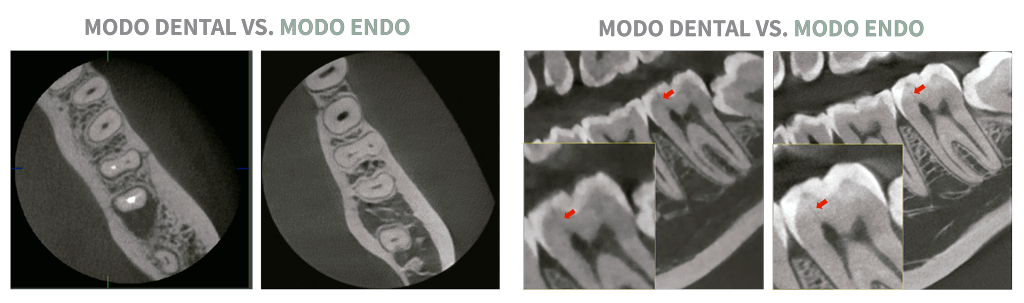

MODO ENDO CON ALTA RESOLUCIÓN VOXEL DE 49.5 MICRAS

Con su modo de volumen de 4 x 4 cm y un tamaño de vóxel de 49.5 micras, modo Endo optimiza el tratamiento de regiones de interés. Es ideal para uso endodóntico porque el dentista puede lograr una imagen extraordinaria en un tamaño de vóxel de alta resolución.